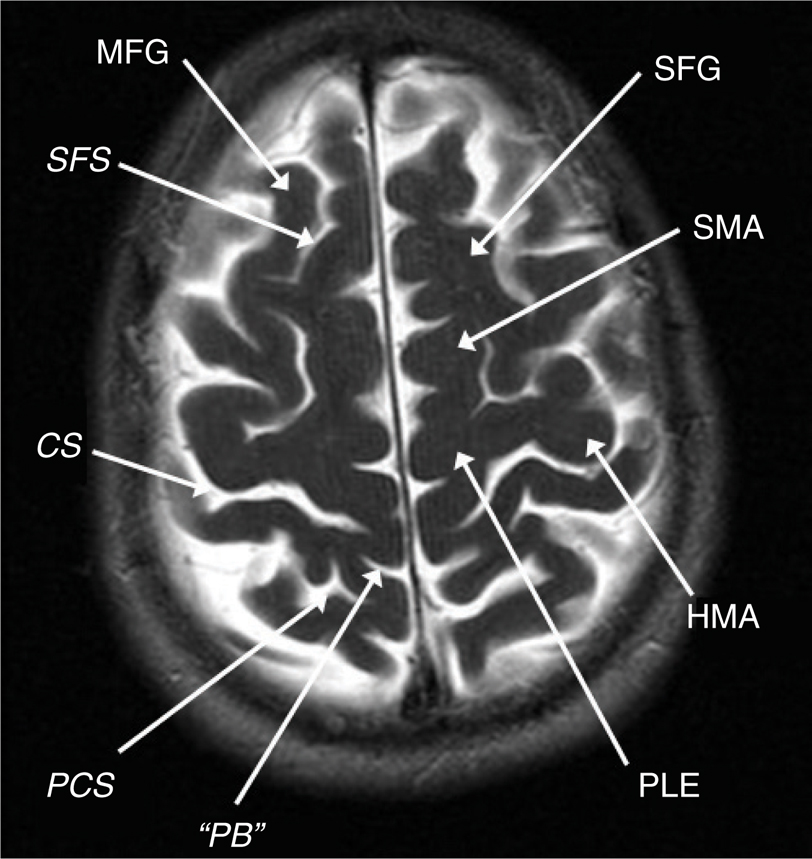

Awake language and motor mapping help reduce morbidity with insular tumor resections, especially on the dominant side (22). The Sylvian fissure is split and the superior and inferior peri-insular sulci provide dissection planes above and below the tumor, respectively. The lateral lenticulostriates define the medial resection plane but are sometimes hard to clearly identify or are obscured by the tumor bulk (22). The safe posterior border is the posterior limb of the internal capsule which may be identified by subcortical stimulation. On the dominant side, resection should not be taken posterior to any language sites. The tumor is resected piece-meal between the MCA perforators in a subpial fashion with sacrifice of small arteries supplying the tumor and insula. Subtle perturbations in motor or speech function truncate the resection at that point. With dominant hemisphere lesions, speech or motor problems may result from frontal or temporal opercular retraction, manipulation spasm of the MCA or interruption of the lateral lenticulostriate or opercular MCA branches, or injury to deep white matter tracts at the superior and medial aspects of the tumor (Figure 4). Nondominant hemisphere resections may have motor weakness through similar mechanisms even though motor function may not be consistently elicited by insula stimulation. With tumors involving the frontal or temporal opercula, a transopercular approach to the insula is a reasonable option (3).

Fig 4

Figure 4 Coronal T2-weighted MRI scan showing the superior frontal gyrus (SFG), middle frontal gyrus (MFG), inferior frontal gyrus (IFG), superior peri-insular sulcus (SPS), inferior peri-insular sulcus (IPS), superior frontal sulcus (SFS), inferior frontal sulcus (IFS), sylvian fissure (SyF), superior temporal gyrus (STG), superior temporal sulcus (STS), middle temporal gyrus (MTG), inferior temporal gyrus (ITG), and collateral sulcus (Colls).